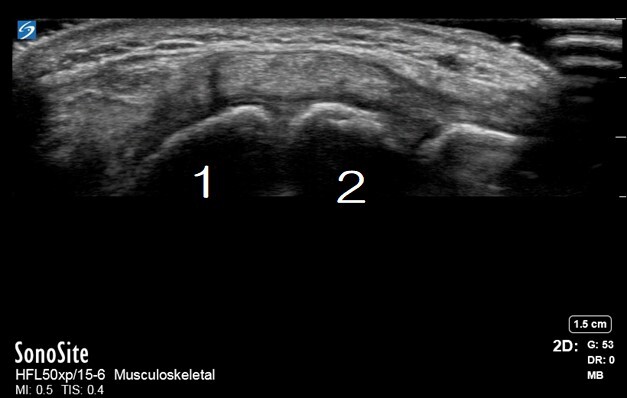

Wrist Scaphoid Lunate Joint Ligament Image

Scaphoid

Lunate

Arrow: Scapholunate joint